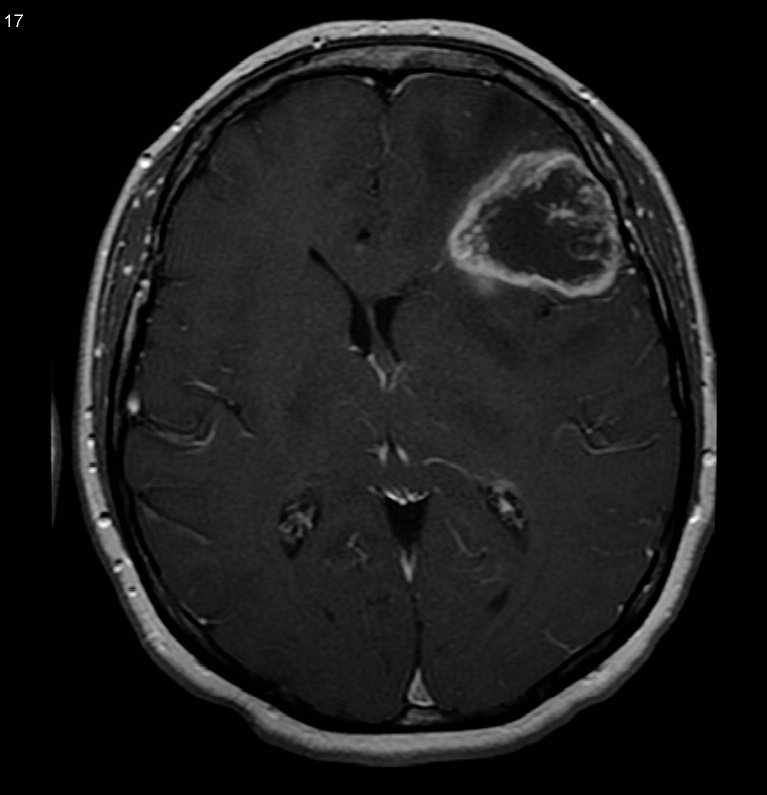

Диагностика заболевания

Так как на ранних стадиях заболевания признаки практически отсутствуют, то диагностирование болезни возможно только с помощью профилактических исследований, к примеру, с помощью онкоскрининга всего тела.

Для получения более полной картины заболевания делается биопсия (гистологическое исследование части головного мозга). Биопсия — сложная нейрохирургическая операция, она проводится под общей анестезией. Когда опухоль локализуется глубоко внутри тканей мозга, биопсия становится невозможной.

Если глиобластома выявлена на ранних стадиях, то есть шанс победить болезнь или немного продлить жизнь человека, имеющего опухоль. После получения результатов анализов и исследований, нейрохирург может назначить лечение индивидуально для каждого пациента.